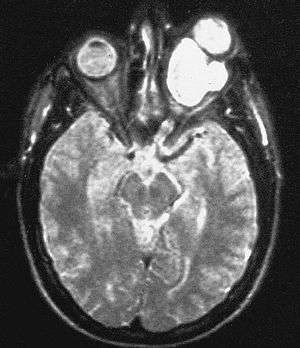

| Magnetic resonance image of a large retrobulbar optic nerve tumor causing massive proptosis. | |

Optic nerve glioma (or optic glioma), a form of glioma which affects the optic nerve, is often one of the central nervous system manifestations of Neurofibromatosis 1.[1][2]

Optic gliomas are usually pilocytic tumors, and can involve the optic nerve or optic chiasm.[3] Optic gliomas are usually associated with neurofibromatosis type 1 in 30% of patients.[3]